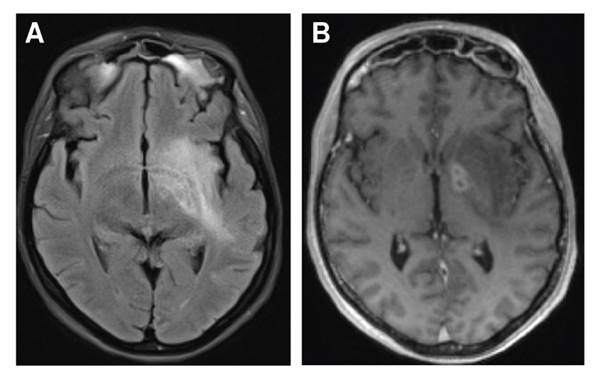

A pesar del manejo antibiótico, 10 días después del ingreso al hospital la paciente presentó hemiparesia izquierda, desviación de la comisura labial con parálisis facial central izquierda y disartria. Se practicó una nueva RM en la que se evidenciaron hallazgos de sinusitis fúngica invasiva con compromiso del espacio masticador, el cavum de Meckel, la fosa craneal media y la órbita izquierda; además, hubo signos de cerebritis y meningitis con trombosis del seno cavernoso izquierdo (figura 1).